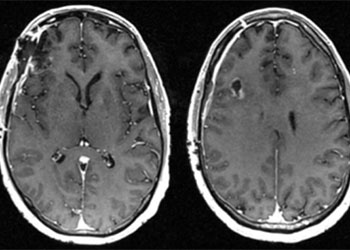

Brain:

Neurosurgeons Collaborate to Treat Giant Symptomatic Meningioma

Author: Ramin Rak M.D., F.A.A.N.S., F.C.N.S., Jonathan L. Brisman M.D., F.A.C.S., Read More!